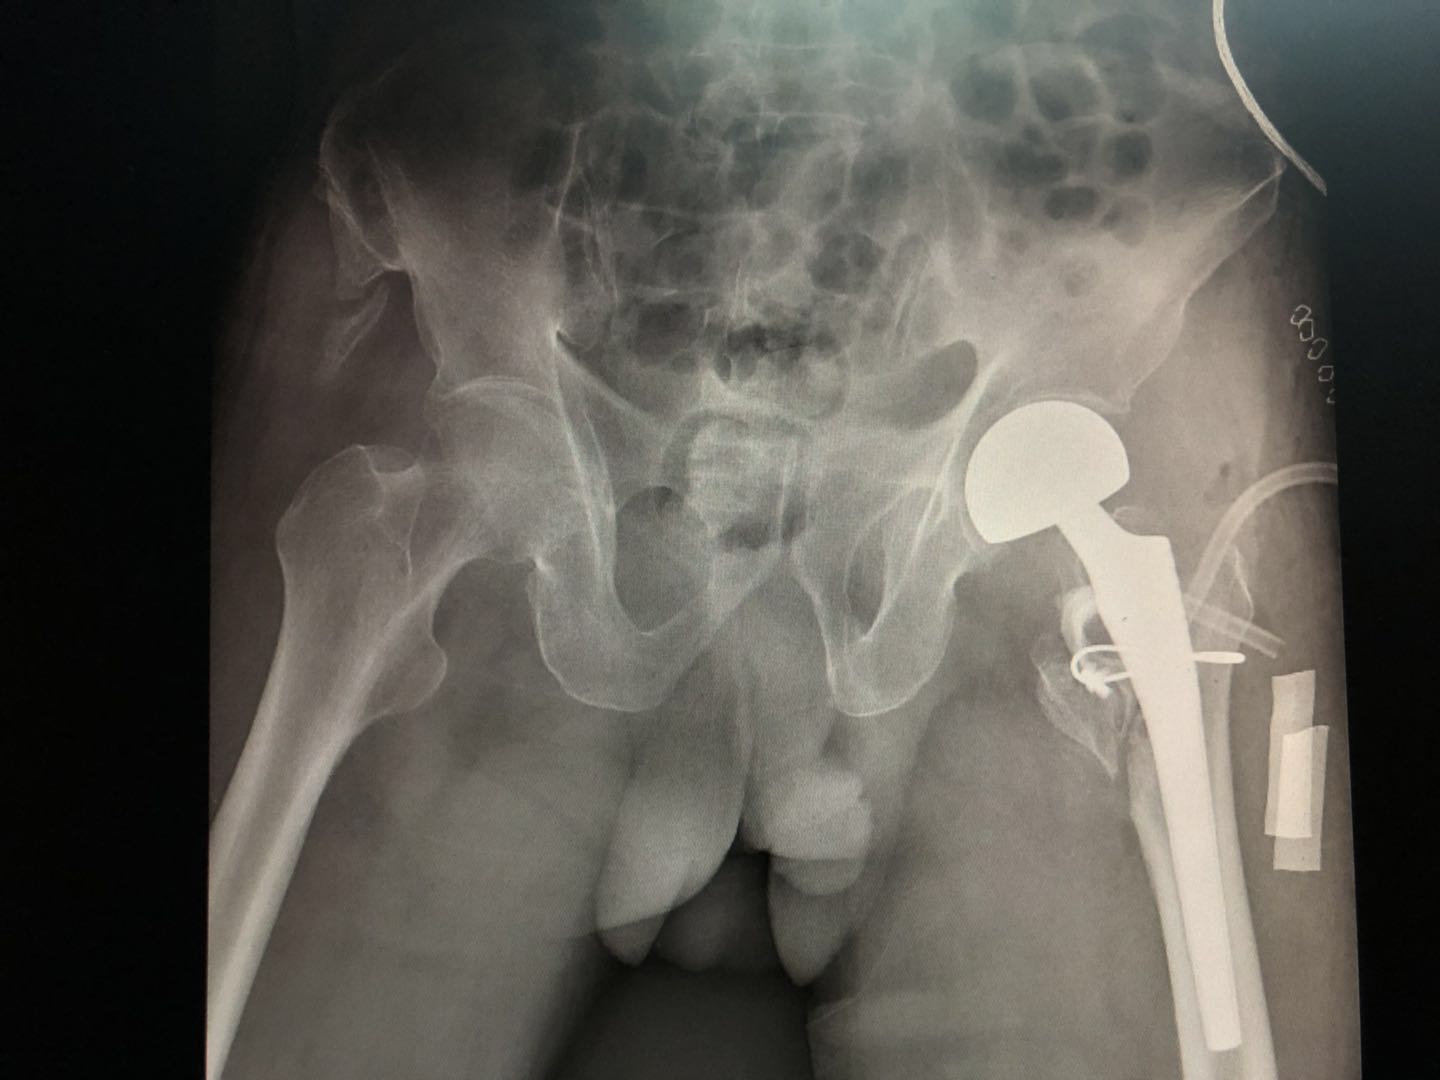

手术很顺利,术后大爷安全返回病房,术后复查了片子如下:

手术后的病理结果如下:

提示股骨头坏死

4、为什么直接就做关节置换手术了,而不是单纯的内固定手术?------单纯的内固定手术保留患者的股骨头,但固定方式基本都是经股骨颈固定,而股骨颈处有营养股骨头的动脉血管,经股骨颈固定必然会影响股骨头的血供,术后患者可能出现股骨头坏死,需要二次手术做关节置换!这对于老年人及其家庭来说,无非是灾难性的。

而冯大爷术后病理结果报告提示冯大爷存在股骨头坏死,也证实了医生选择直接行关节置换手术是对的。